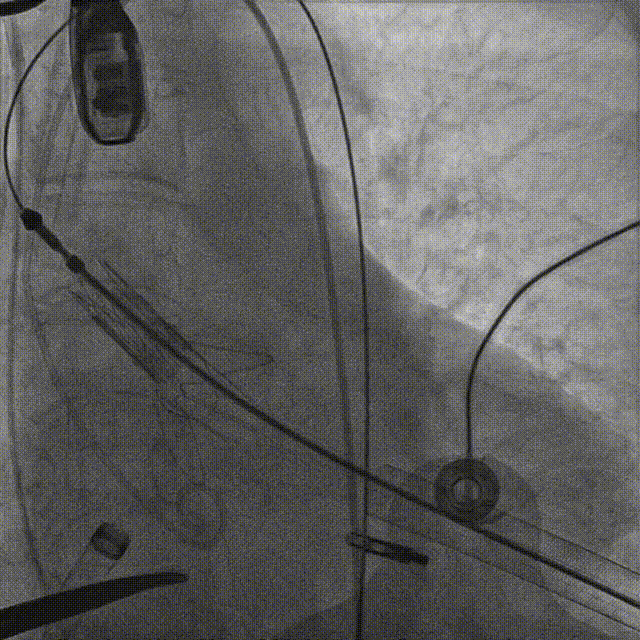

导丝进行房间隔穿刺:

CDS放置在二尖瓣处:

打开夹子,调整弹道垂直于二尖瓣瓣环:

将MitraClip推进至左心室,捕获瓣叶:

捕捉瓣叶后,经超声心动图确认瓣叶夹持牢固,释放瓣膜夹: